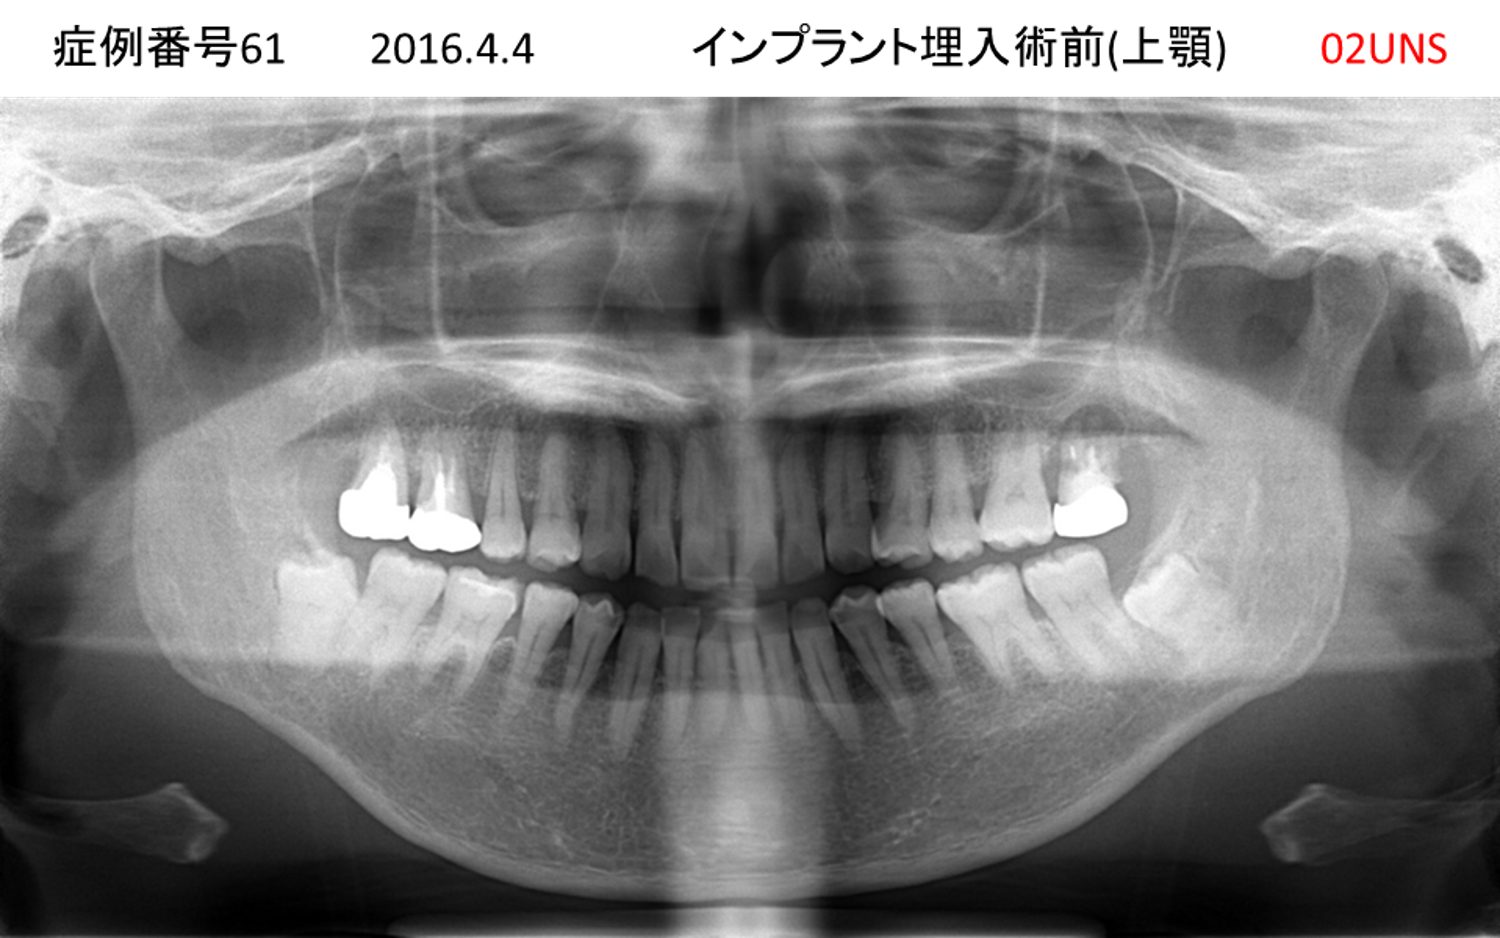

上の前歯が揺れてきてかめない患者様のインプラント症例

| 治療名称 |

インプラント |

| 治療費用 |

440万円+税 |

| 治療期間 |

6か月 |

| 患者さんの症状(主訴) |

上の前歯が揺れてきた。かめない |

| 治療内容 |

サイナスリフト、GBR、インプラント、即時荷重 |

| 治療結果 |

上の前歯の揺れが収まった。奥歯でしっかり噛める。 |

| 治療の注意点(リスク/副作用) |

インプラントが壊れたら再治療が必要 |